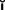

Fig. 6-1 Sequence of treatment. A, The patient has pain that seems to originate from the maxillary right central incisor. In addition, several teeth are missing, and retained roots, caries, calculus, and defective restorations are present. B, Relief of the acute problem by endodontic treatment of the incisor. C, Removal of deposits and unrestorable teeth. D, Caries are controlled, and defective restorations are replaced. The progress of ongoing disease has been halted. E, Endodontic treatment is undertaken, and post and cores and an interim restoration are placed. F, Definitive periodontal treatment is performed. G, Teeth are prepared for the final restoration. H, The fixed restorations are completed. I, Active phase of the treatment has been accomplished. Note that predictable management of complex prosthodontics involving fixed and removable dental prostheses can be facilitated by adopting the technique described on p. 102.